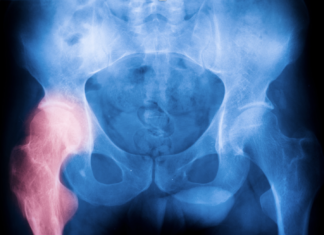

Anca dolorosa, SIOT: «Ecco quando ricorrere alla protesi»

Dolore persistente all’anca e difficoltà nei movimenti quotidiani sono segnali da non sottovalutare. Ma che cosa si intende davvero con "anca dolorosa"?...